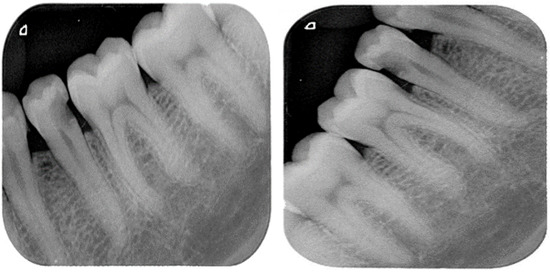

| Lesion Type | Images |

|---|---|

| Primary Endo with Secondary Perio | 122 |

| Primary Endodontic Lesion | 124 |

| Primary Perio with Secondary Endo | 39 |

| Primary Periodontal Lesion | 118 |

| True Combined Lesions | 131 |

| Total radiographs | 534 |